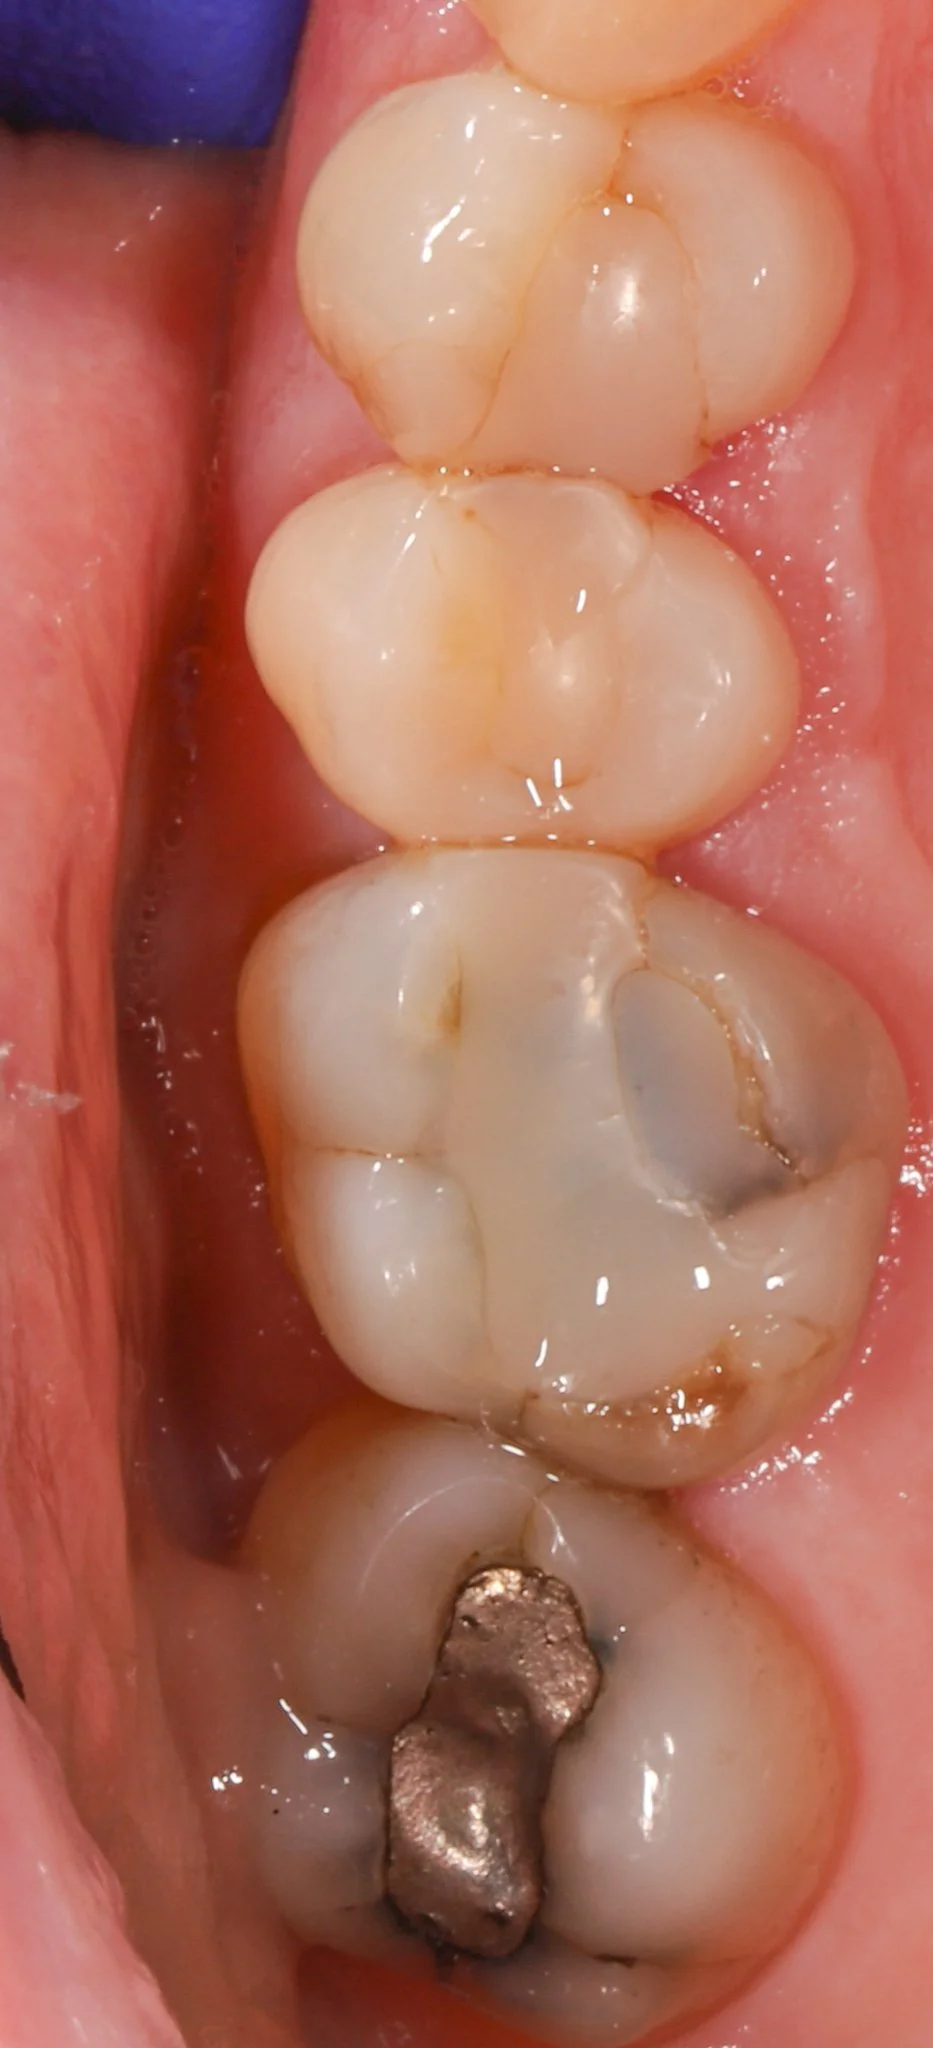

Close-up of molar teeth with signs of decay, leakage and cracks. Prior to restorative treatment.

Before: Leaking fillings, decay, cracked teeth

Close-up of molar teeth after restorations with bonded porcelain crowns showing optimal dental health.

After: New teeth blend seamlessly